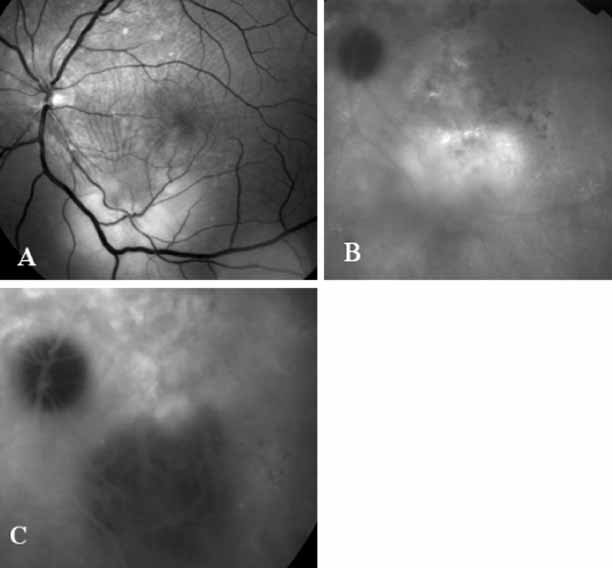

Although initially reported exclusively in middle-aged, black females, PCV has since been recognized as a variant of CNV that can be found in all patients with AMD. This entity is characterized by the presence of an inner choroidal vascular network ending in an aneurysmal bulge clinically seen as a red–orange, spheroid, polyp-like structure. Leakage and bleeding from the choroidal vascular abnormalities result in multiple, recurrent, serosanguinous RPE detachments.25,39,40,41 ICG can be used to identify and characterize the vascular abnormality with high sensitivity and specificity.19–21,40–59 Early-phase images of the lesions show a distinct network of vessels within the choroid. Patients with juxtapapillary involvement show a radial, arching pattern with an inner network of vascular channels extending and connecting with smaller, spanning branches that are more numerous and increasingly prominent at the edge of the PCV lesion.

Larger choroidal vessels in the PCV lesion begin to fill before retinal vessels but appear to fill at a slower rate than the retinal vessels. The lesion initially appears noticeably hypofluorescent relative to the surrounding, uninvolved choroid, but soon after the network is first visible with ICG angiography, small, hyperfluorescent “polyps” can be seen within the choroid. These polypoidal structures correspond to the red–orange choroidal excrescence seen clinically. They leak slowly into the surrounding hypofluorescent area, creating increasing hyperfluorescence. In the late phases of the ICG angiogram, a uniform washout pattern is seen as the dye disappears from the polypoidal vascular structure; the late-staining characteristic of occult CNV is not seen in PCV. PCV may be localized to the macular area without any peripapillary involvement. It may present as a network of small branching vessels ending in polypoidal dilation best-imaged with ICG angiography. (Fig. 12)